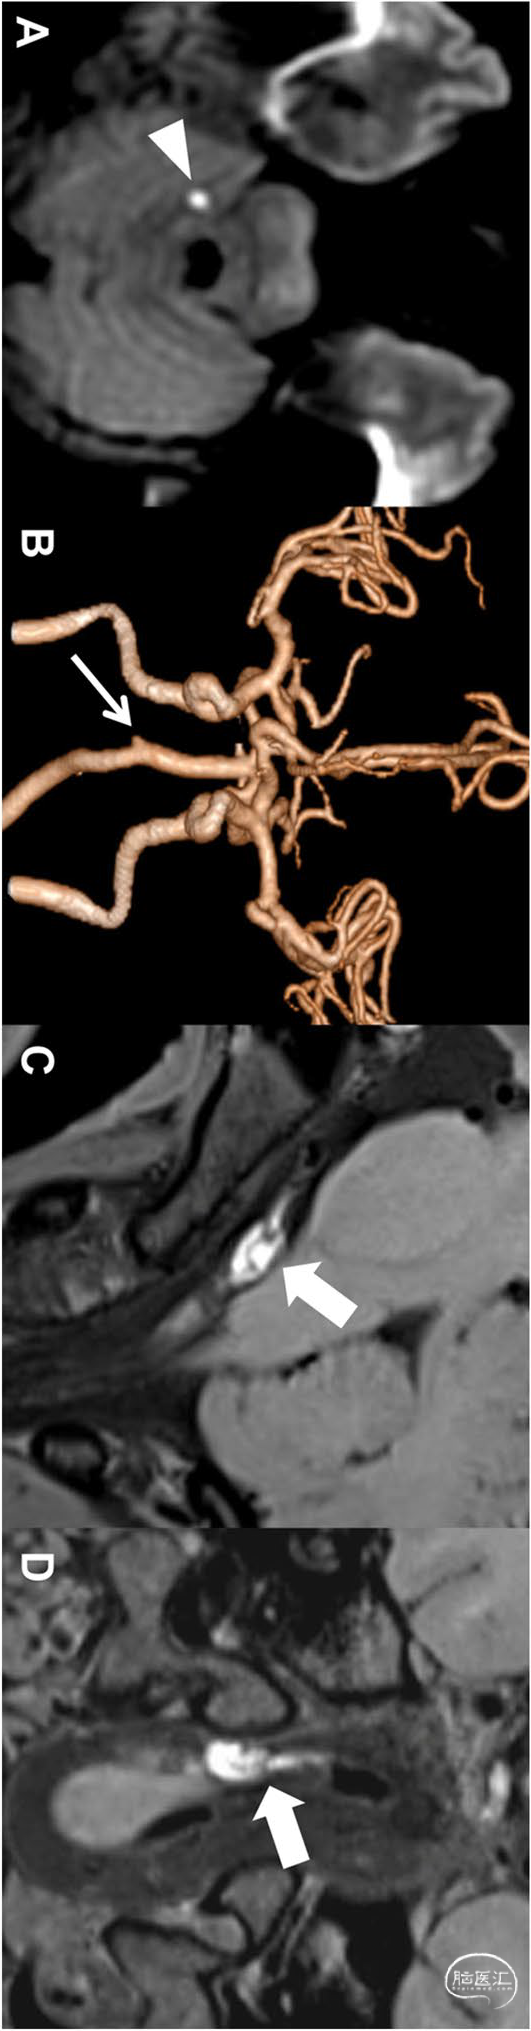

女性,19岁。表现为头痛、头晕和呕吐。无传统的危险因素。DWI显示右小脑高信号,梗死(A,箭头)。CTA显示右椎动脉V4段闭塞(B,细箭头)。根据传统检查,该患者诊断为病因不明卒中。然而,平扫HRVWI(C和D)可见右侧椎动脉的壁间血肿和血栓形成(C和D,粗箭头)。加入HRVWI后,卒中病因变为其他确定病因的卒中(动脉夹层):